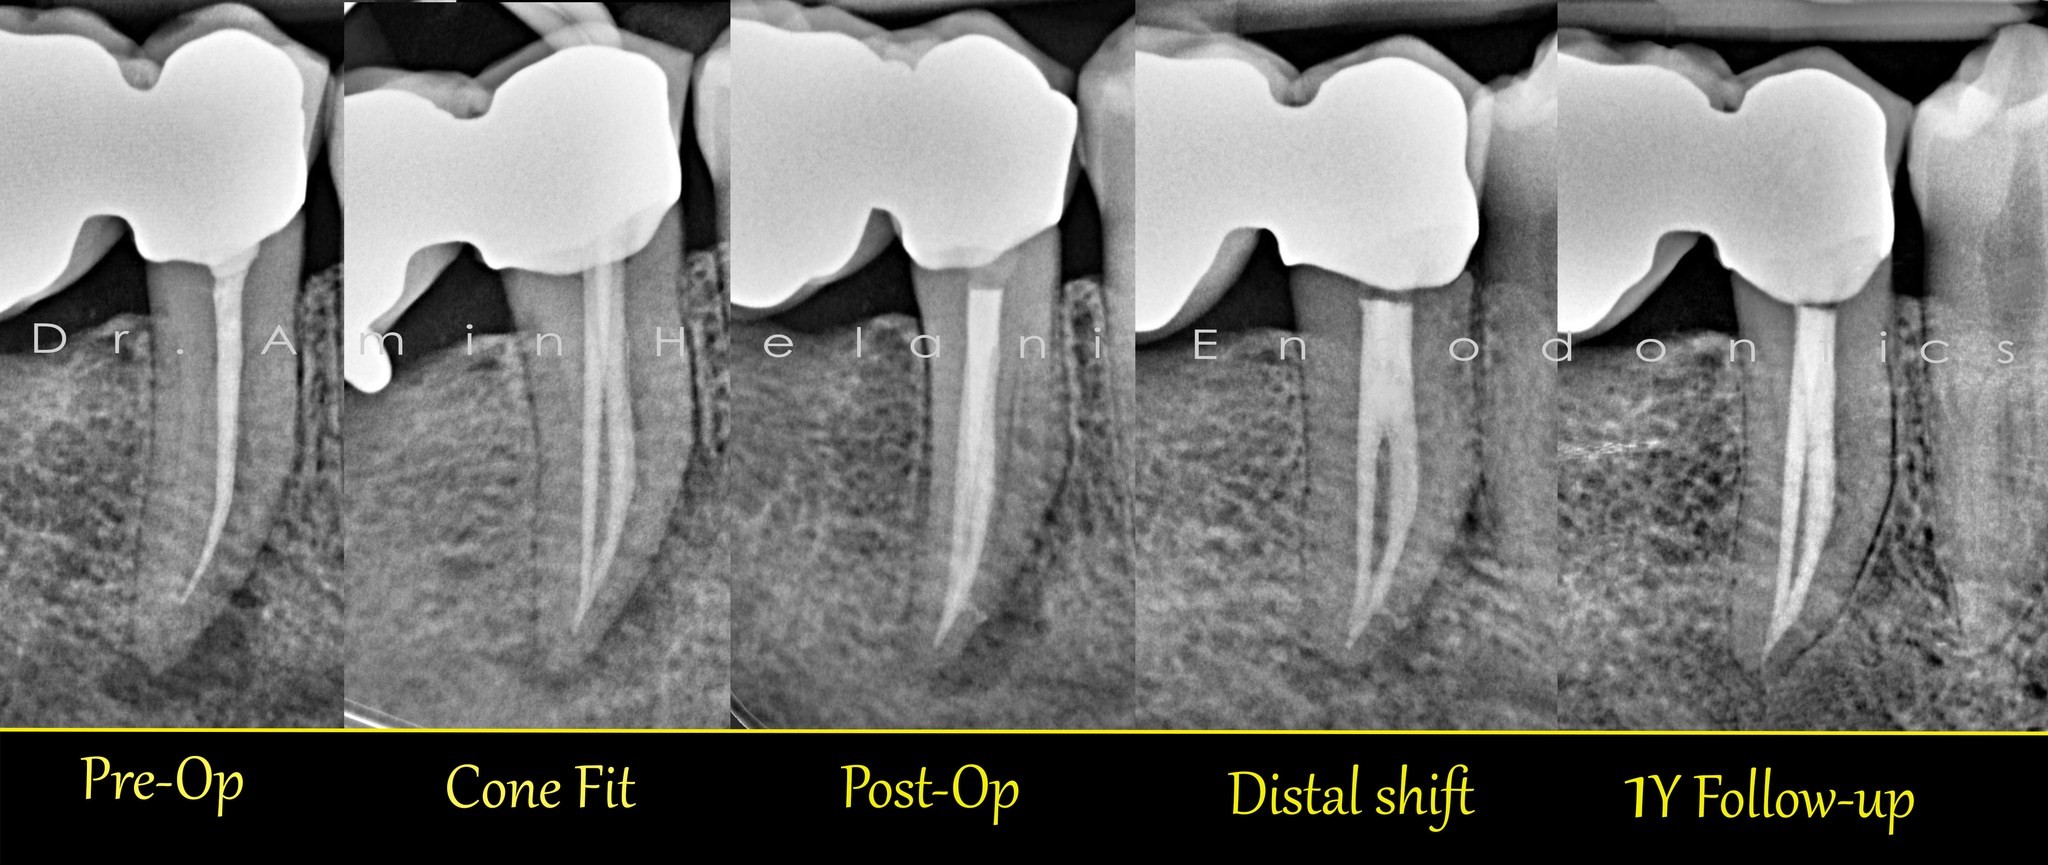

tiefe Aufteilung + Heilung